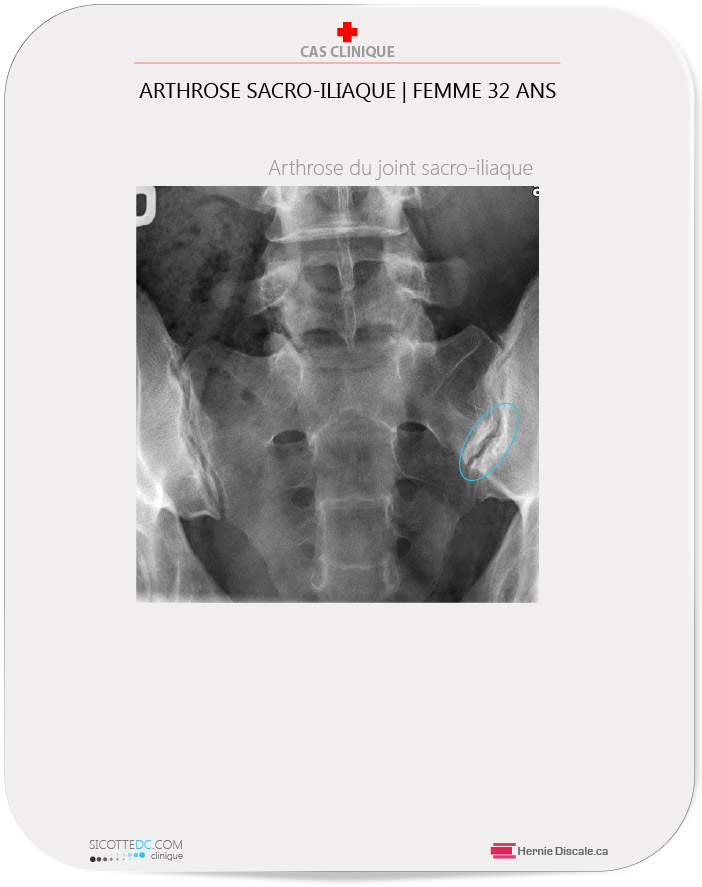

arthrose,